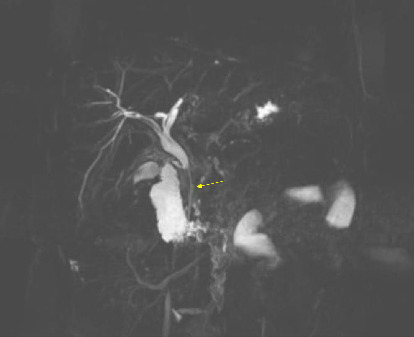

Abstract Image